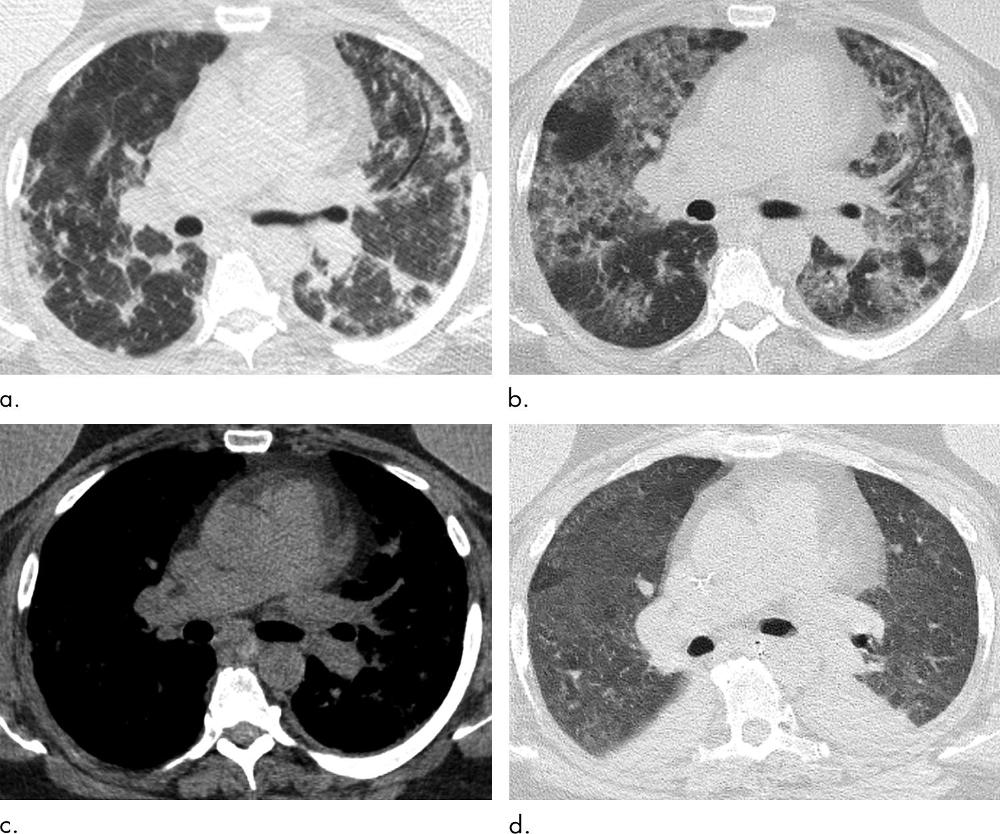

Figure 12. Images show multiple episodes of electronic cigarette or vaping product use–associated lung injury due to repeated vaping of nicotine with mint flavoring in a 51-year-old woman. Bronchoalveolar lavage (BAL) fluid showed numerous foamy lipid-laden macrophages with positive Oil-Red-O lipid staining. (a) CT in September shows organizing pneumonia pattern with scattered areas of ground-glass opacity with subpleural sparing. Workup for infection was negative, and patient was started on steroids and improved. (b) Two months later, patient returned to emergency department with dyspnea and fever. CT image shows more extensive ground-glass opacity with areas of lobular and subpleural sparing. Interlobular and intralobular septal thickening is present, creating “crazy paving” pattern. (c) Although patient’s BAL fluid showed many lipid-laden macrophages, soft-tissue image shows no evidence of intraparenchymal fat attenuation, a common finding in lipoid pneumonia. Patient’s condition deteriorated, and she was intubated and started on steroids. (d) Ten days after initiation of steroids, ground-glass opacity has improved but persists. Patient’s condition was complicated by aspiration pneumonia and bilateral lower-lobe collapse.

High-res (TIF) version